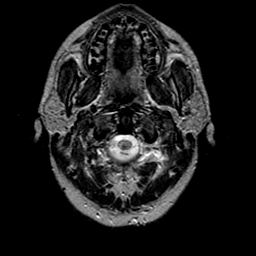

glioma overlay -- Slice #0

[Home][Help][Clinical] Slice 0